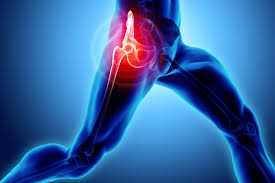

고관절 통증은 “허리 아픈가?” “무릎 아픈가?” 헷갈리게 시작하는 경우가 많습니다. 실제로 고관절은 통증이 사타구니(서혜부), 엉덩이, 허벅지 옆, 심지어 무릎까지 번져 느껴지기도 하거든요. 그래서 “증상 모양”을 먼저 정리해두면, 불필요한 걱정은 줄이고 필요한 진료는 빠르게 잡을 수 있습니다. 오늘은 고관절 통증 증상을 아주아주아주 쉽게 풀어드릴게요.

고관절 통증이 자주 나타나는 위치

• 사타구니가 깊게 아픔 : “관절 안쪽” 느낌이 강하면 고관절 자체 문제(관절염, 충돌증후군, labrum 등) 가능성을 생각합니다.

• 엉덩이/뒤쪽 통증 : 허리(요추) 문제와 구분이 필요할 수 있어요.

• 허벅지 바깥쪽(골반 옆 ‘뼈 튀어나온 곳’)이 아픔 : 옆으로 누우면 더 아프고, 눌렀을 때 통증이 심하면 점액낭염(대전자 점액낭염) 쪽이 흔합니다.

• 무릎까지 뻗는 통증 : 고관절 통증이 “무릎”으로 느껴지는 경우도 있어 위치만으로 단정하긴 어렵습니다.